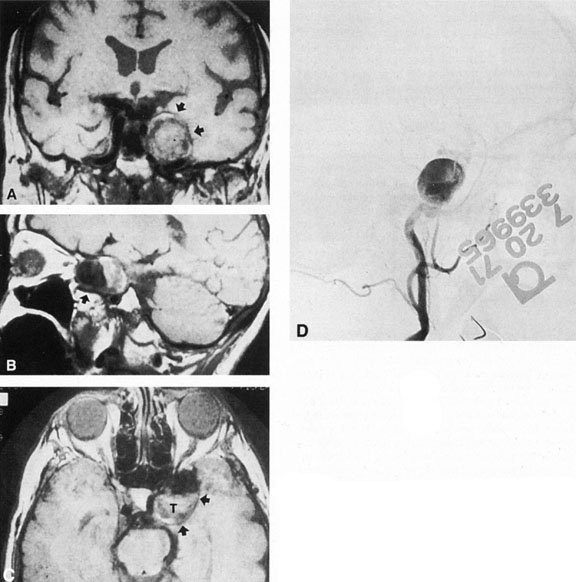

Fig. 3. Magnetic resonance images of intracavernous aneurysm in a 72-year-old woman with left retrobulbar pain and sixth-nerve palsy. A: Coronal section (TR, 800 ms; TE, 30 ms). B: Parasagittal section (TR, 1000 ms; TE, 20 ms). C: Axial section (TR, 800 ms; TE, 30 ms). Note partial occlusion by thrombus (T). D: In a similar patient, carotid arteriogram (subtracted, lateral view) demonstrates a large intracavernous aneurysm.

Fig. 4. Giant suprasellar (supraclinoidal) aneurysms. A: Carotid arteriogram (lateral view) shows a huge aneurysm of the internal carotid artery in a 59-year-old woman with progressing visual loss. Coronal (B) and axial (C) magnetic resonance imaging sections of a similar case. Note partial thrombus formation (TR, 2100 ms; TE, 80 ms).